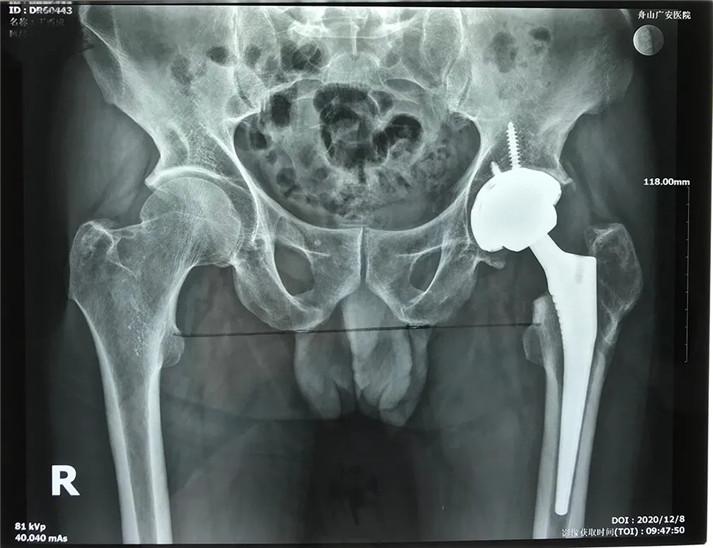

經(jīng)過(guò)周密的術(shù)前準(zhǔn)備,在身體符合手術(shù)指征后,丁大哥接受了全髖關(guān)節(jié)置換術(shù)。術(shù)中發(fā)現(xiàn)術(shù)前規(guī)劃產(chǎn)生的假體大小、位置、角度均非常理想,大大縮短了手術(shù)時(shí)間,全程十分順利。術(shù)后,丁先生恢復(fù)良好,次日即可下床活動(dòng)。目前術(shù)后一個(gè)月,可以干活了。對(duì)于此次手術(shù),丁大哥及其家屬表示非常滿(mǎn)意。

術(shù)后